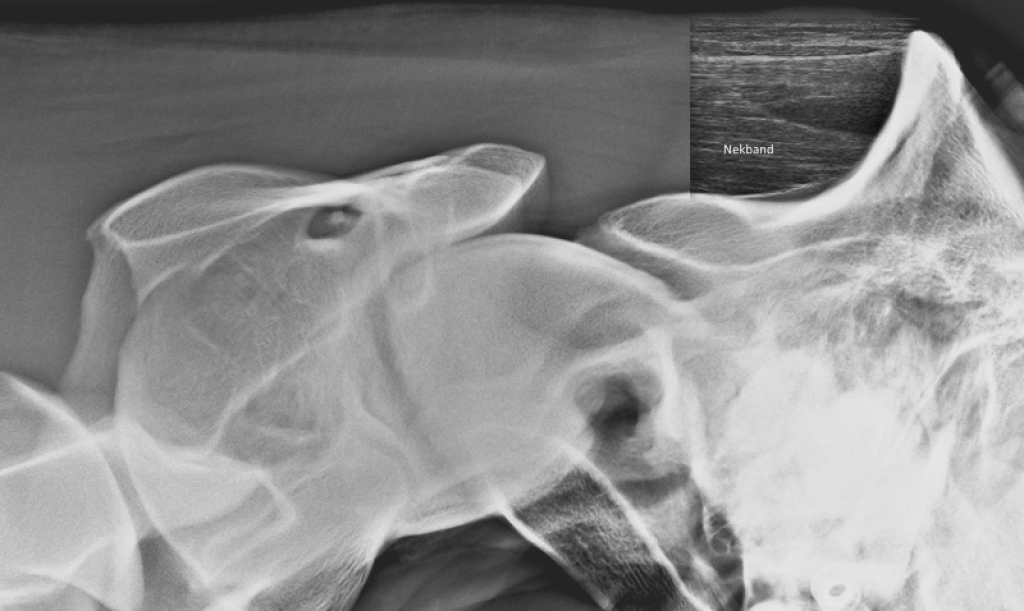

Links: Röntgenfoto van benige nieuwvorming op het achterhoofd

Rechts: Echografie van de nekband van hetzelfde paard als de röntgenfoto

Röntgenfoto van benige nieuwvorming op het achterhoofd

Echografie van de nekband van hetzelfde paard als de röntgenfoto